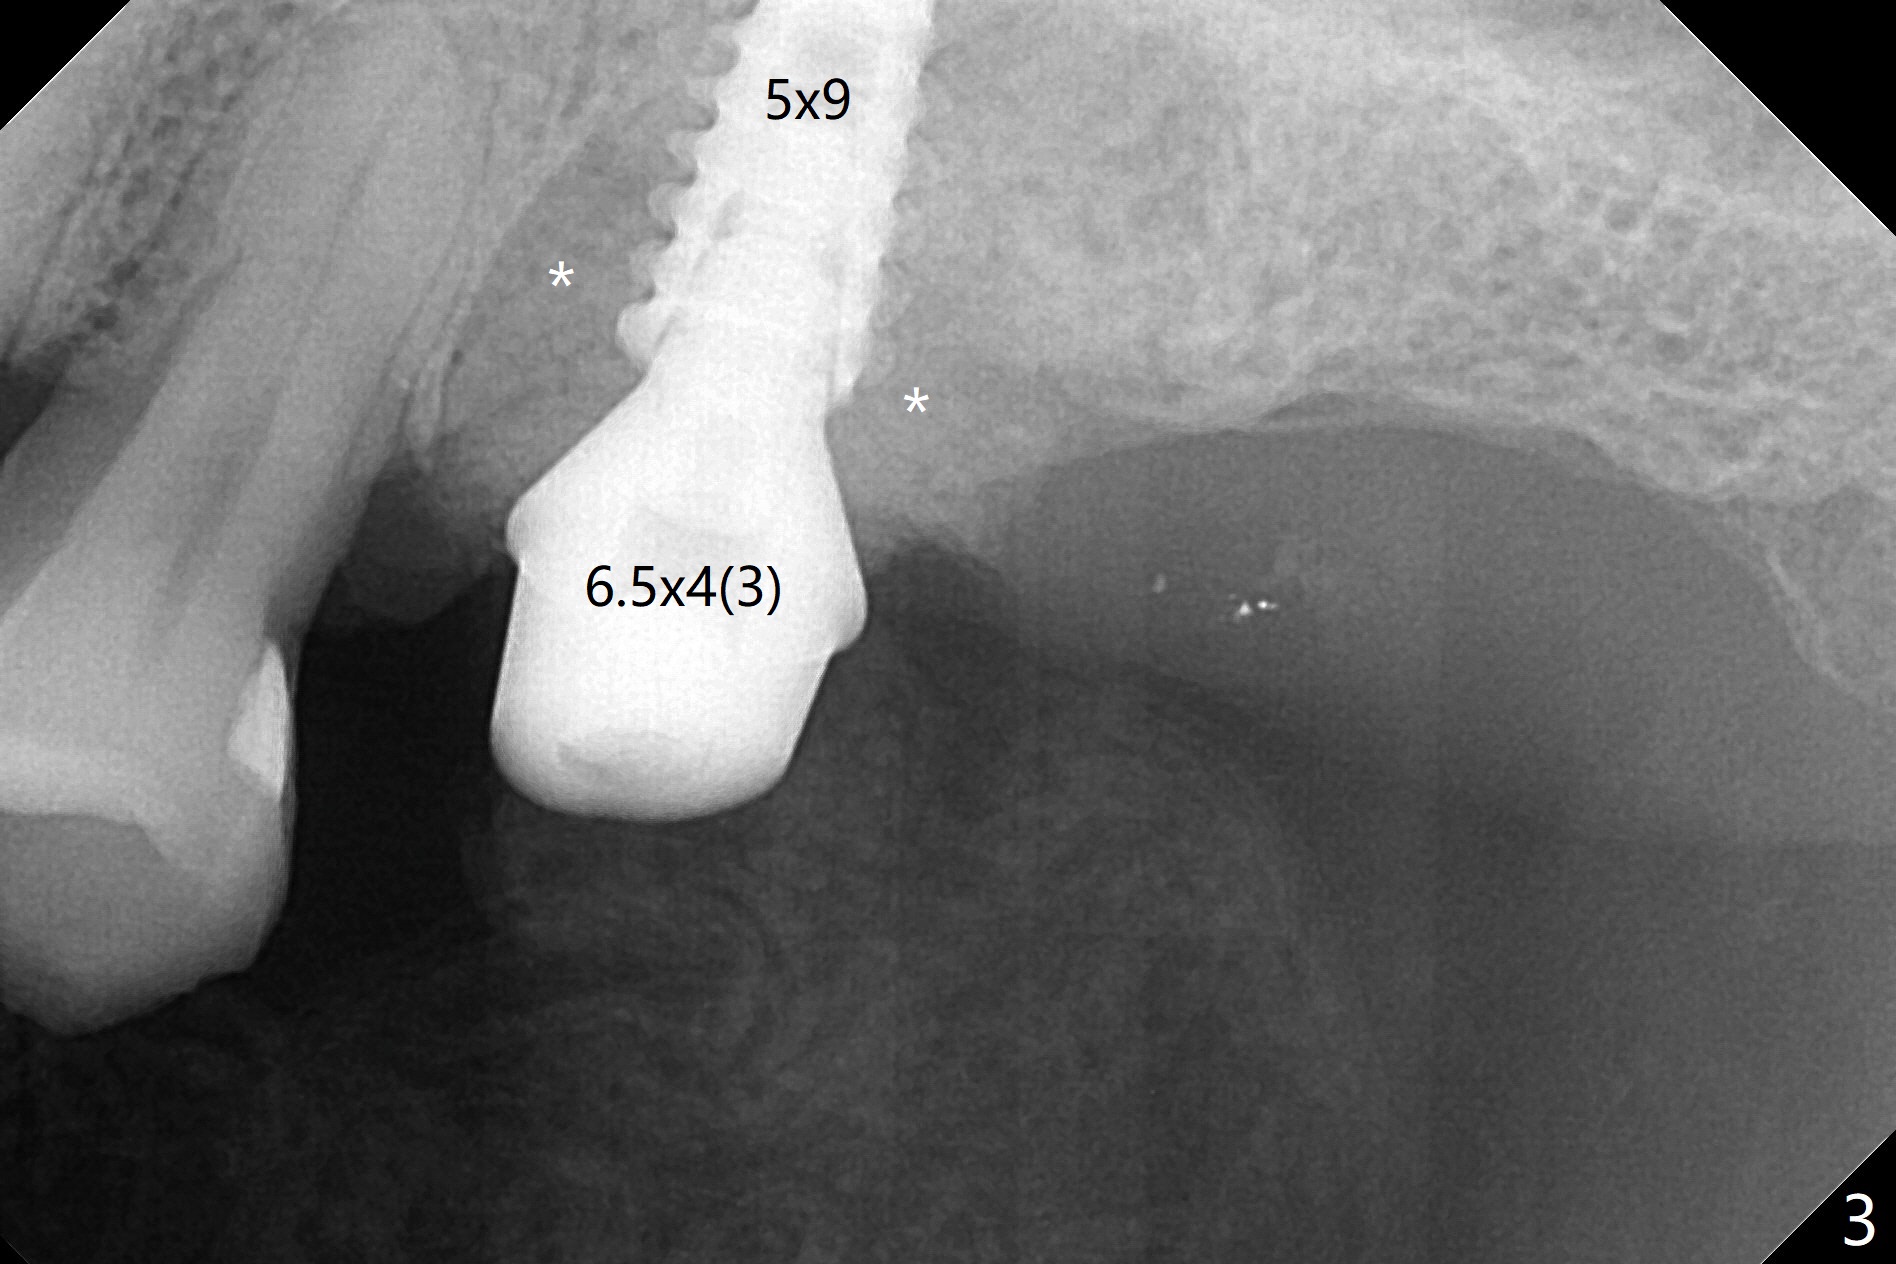

After extraction of the tooth #14 (Fig.1) and removal of granulation tissue associated with a distal fistula, a 1.6 mm drill is used to initiate osteotomy in the septum for 9 mm, followed by insertion of a 7 mm long parallel pin (Fig.2). The length of the subsequential osteotomy is 11 mm until 4.8 mm in diameter (overprep as will be shown below). The bone is hard so that sinus lift fails with 4.8 mm Magic Expander. Since a 5x9 mm dummy implant is placed with stability, a definitive implant with the same dimension is chosen with >50 Ncm (Fig.3,4). Prior to and after abutment placement, Vera graft is placed (*). The provisional perforates with loose abutment 3.5 months postop. A 6x4 mm healing abutment is placed. Osteointegration occurs 4 months postop (Fig.5,6).